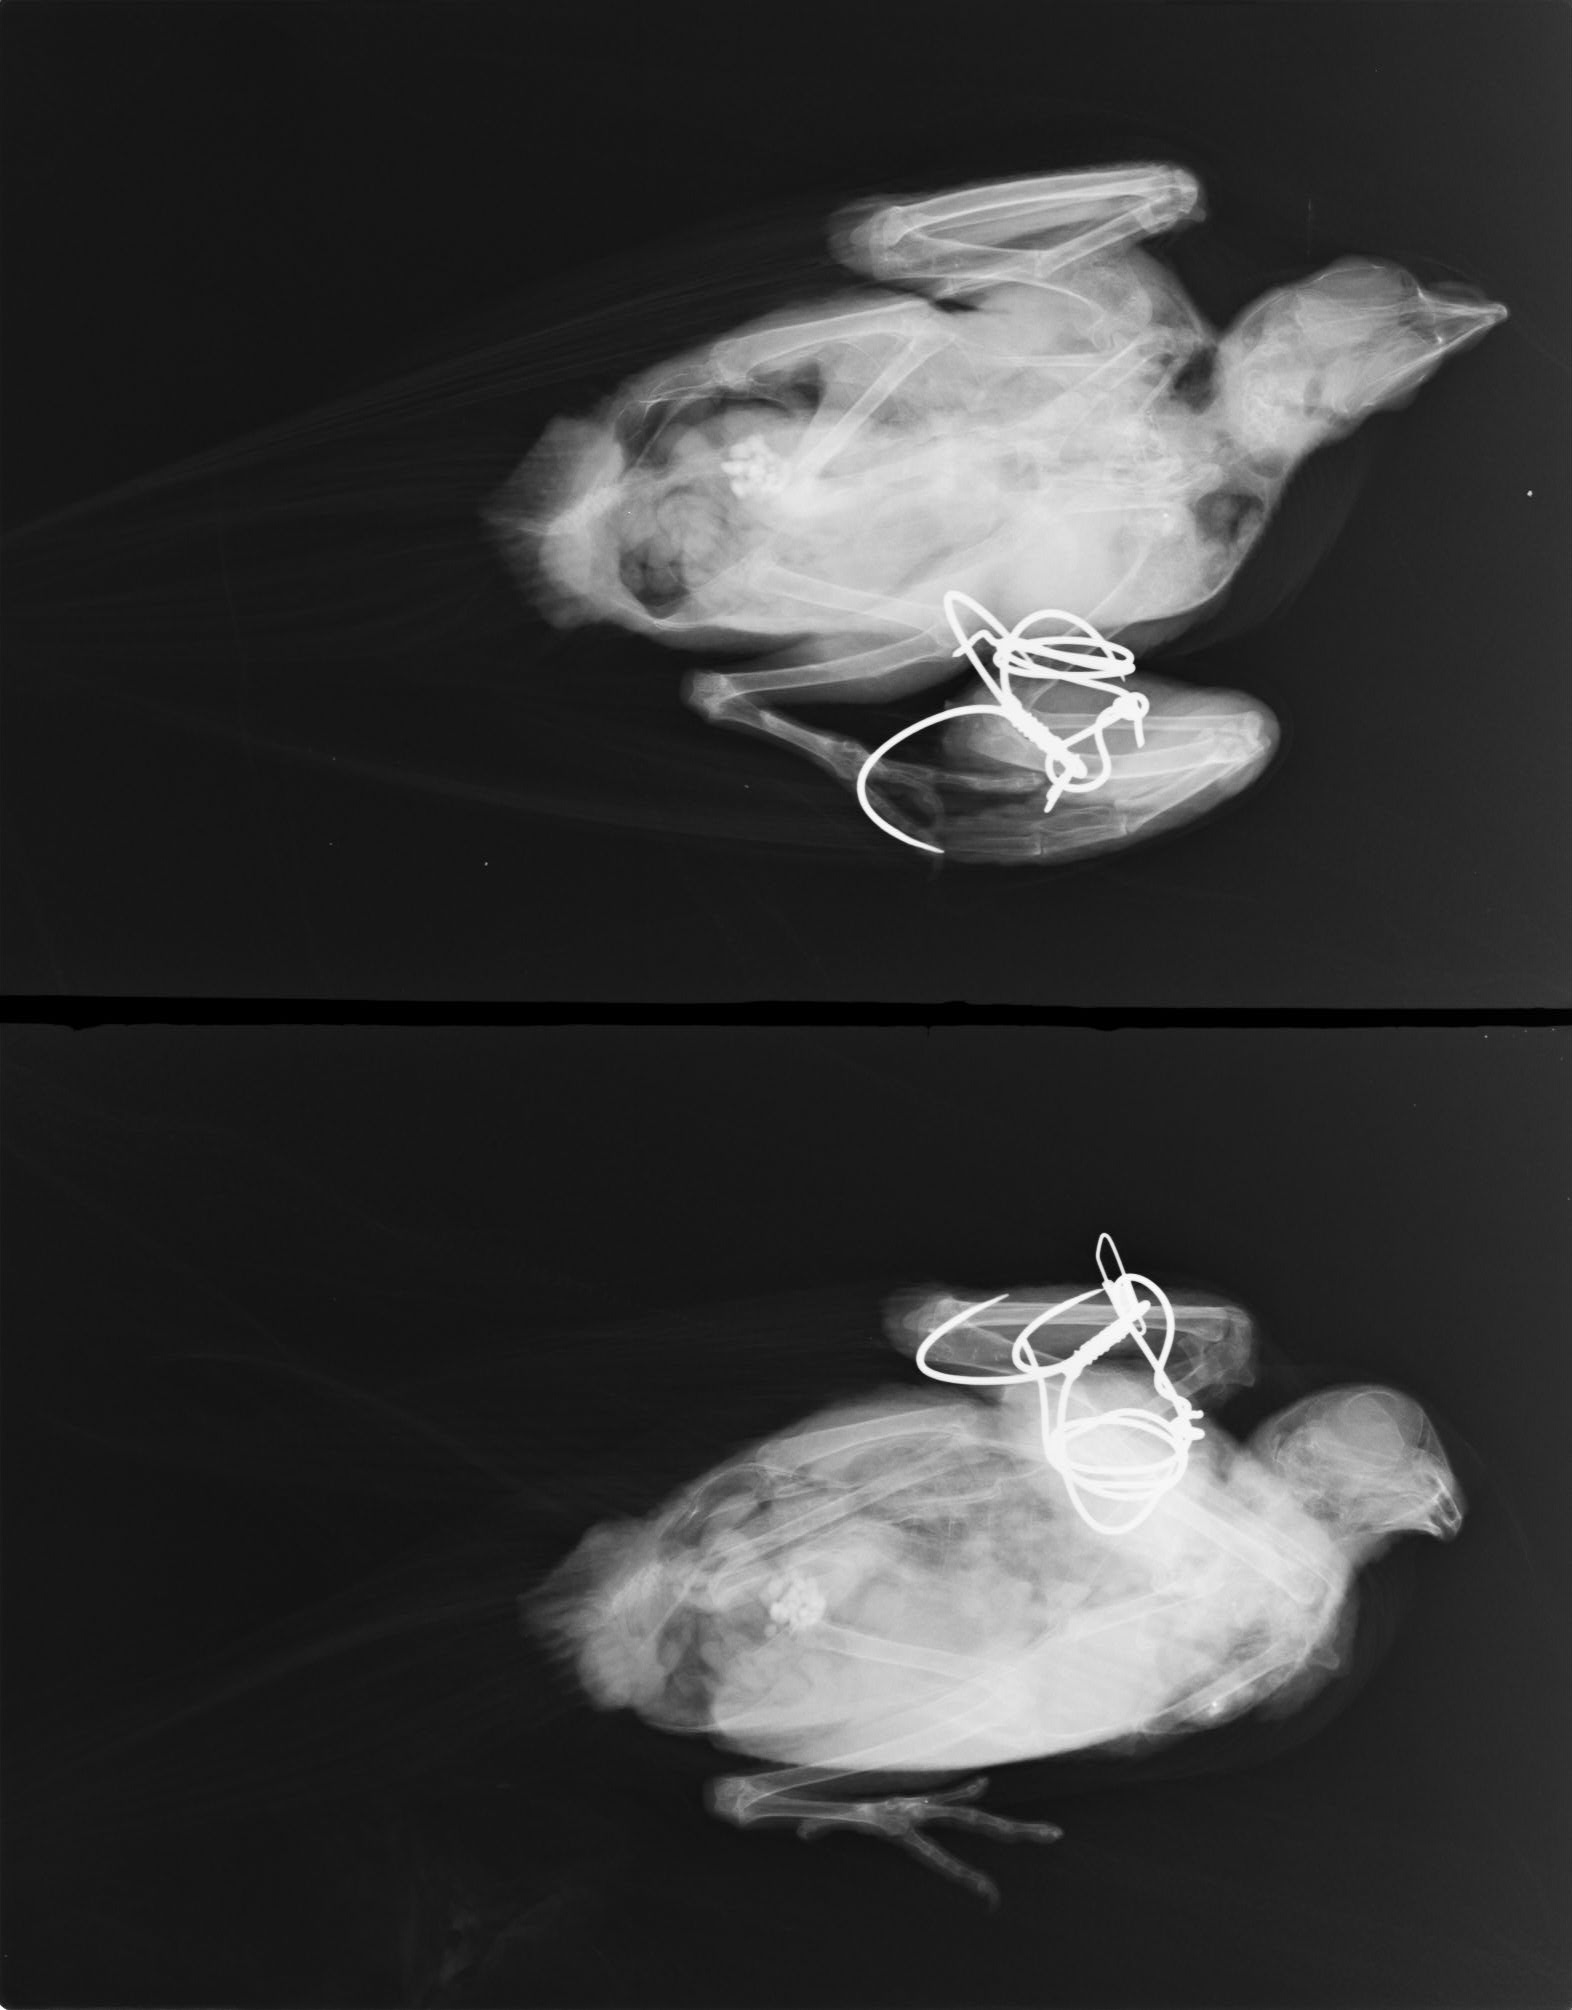

野鳥保護でハトをあずかりました。右ひじ部に針金が絡んでいます。

うまく飛べないようです。食い込んでいてよくわからないのでレントゲンとってみました。

ひっかけ釣り用の針金が絡んで3回巻きついているようです。